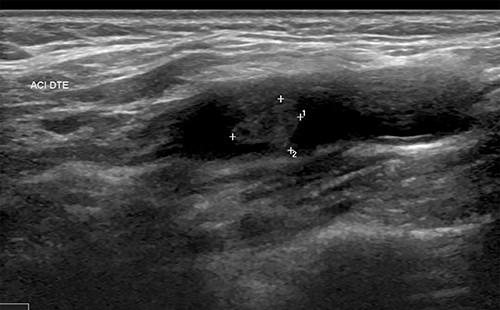

| • Supra-aortic trunks and cerebral arteriography: typical aspect of carotid diaphragm | • Supra-aortic trunks echo Doppler + agioscanner: carotid diaphragm with floating thrombus of the right carotid artery(Fig. 1) | • MRI and supra-aortic trunks angiogram: carotid bulb thrombus (Figs 2 and 3) | • Angioscanner: very suggestive of carotid diaphragm |

Doppler of the supra-aortic trunks also helps to approach the diagnosis. The lesion is usually described as an elevated intimal layer followed by a cone or shelf shaped intraluminal defect located on the proximal and posterolateral side of the bulb of the internal carotid artery [6]. It appears moderately hyperechoic and may reveal the presence of thrombi. Ultrasound remains a widely available non-invasive examination, but the results depend on the expertise of the operator. According to some case series, carotid diaphragms are often misdiagnosed or underdiagnosed by the ultrasound doppler [7], which is probably due to their small size, non-limiting aspect and lack of operator awareness of this entity. Multimodal magnetic resonance imaging (MRI) allows the exploration of the carotid wall and could allow, on the basis of further studies, to differentiate the carotid diaphragm from other lesions such as atherosclerotic plaques [6]. Angiography can be considered as the ‘gold standard’ for the diagnosis of the carotid diaphragm because of its high spatial and temporal resolution. It allows analysis of haemodynamic features, many of which have been reported as persistent contrast stasis at the rostral level of the lesion. Management of carotid diaphragm can be surgical, endovascular or medical. Surgical treatment consists of focal excision of the carotid segment where the dysplasia is located followed by artery-arterial anastomosis. It has the advantage of allowing a histopathological examination confirming the dysplastic nature of the lesion. Carotid artery stenting is an endovascular method whose aim is to flatten the defect and avoid blood stagnation. It was initially described in two cases in 2014 [12]. Carotid stenting is performed under dual antiplatelet therapy, usually maintained for three months, followed by long-term monotherapy [13]. Pretreatment with anticoagulant is performed for cases associated with the presence of a thrombus. Compared with surgery, stenting is more recent but proved to be efficient in preventing stroke. A retrospective review of 24 patients admitted to five comprehensive stroke centers conducted by Haussen et al. [13] showed that stenting for symptomatic carotid diaphragm appears to be a safe and effective alternative to surgical resection. Medical treatment alone with anti-platelet agents and anticoagulants is associated with a high risk of recurrence.